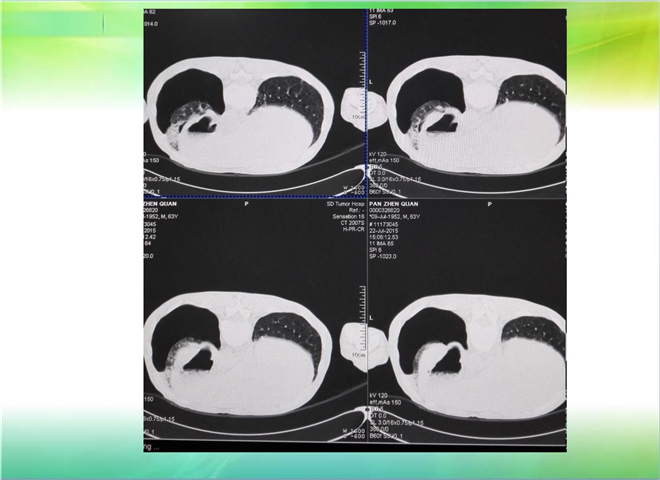

CT引导下穿刺活检术